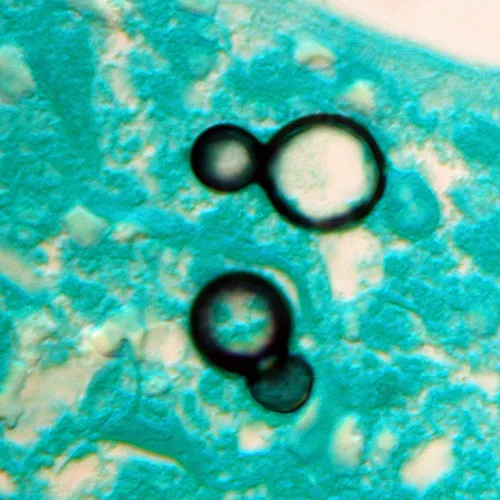

- Blastomyces: Broad-based budding yeast.

- Blastomycosis is identified by its characteristic broad-based budding yeast.